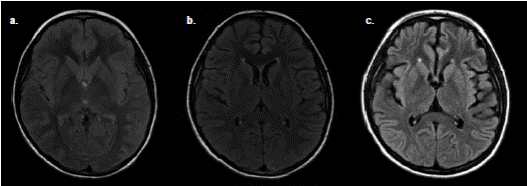

En el examen físico se evidenció afasia, lateralización de la marcha a la izquierda y disdiadococinesia izquierda. Durante la observación, se manifestaron movimientos bruscos con desviación oculocefálica a la derecha y postura distónica en las cuatro extremidades. La paciente se tornó estuporosa, lo cual motivó su ingreso en la unidad de cuidados intensivos pediátricos. La TC simple de cráneo, la RM cerebral simple (figura 2) y el electroencefalograma (EEG) inicial no evidenciaron alteraciones, pero el EEG posterior evidenció una lentitud en el rango delta difuso, y el examen citoquímico del líquido cefalorraquídeo mostró pleocitosis polimorfonuclear (cuadro1).

Figura 2 Resonancia magnética cerebral simple con serie de cortes axiales en secuencia FLAIR de la paciente del caso 2. a. Estudio realizado en el momento de su ingreso al hospital; no se observan alteraciones en el parénquima cerebral. b. Estudio realizado cuatro meses después de su ingreso; se aprecia pérdida incipiente del volumen cerebral debida a un mayor crecimiento de los ventrículos y a la ampliación del tamaño de los surcos cerebrales. c. Estudio realizado 11 meses después del inicio de sus síntomas, en el cual se observa una pérdida mucho mayor de volumen cerebral en comparación con los anteriores.